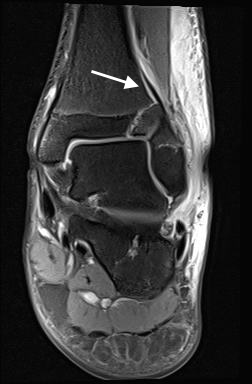

Fugengelenkfrakturen treten typischerweise vor dem 10. Lebensjahr auf, in einer Phase, in welcher die Wachstumsfugen noch weit offen sind. Dieser Frakturtyp betrifft fast ausschließlich den medialen Malleolus. Laterale Frakturen sind extrem selten, teilweise kommt es zu lateralen Bandverletzungen oder Fugenschaftfrakturen der distalen Fibula. Die Frakturlinie verläuft in einer Verlängerungslinie von der medialen Taluskante nach proximal. Häufig stellen sich Verletzungen des Innenknöchels im Röntgenbild schlechter dar, insbesondere wenn die Aufnahmen verdreht sind oder die Ebene der Fraktur bei geringer Dislokation verkippt zur Röntgenebene liegt. Besteht klinisch der geringste Hinweis auf eine Verletzung des Innenknöchels, muss aufgrund der Tragweite der Verletzung durch entsprechende Aufnahmen gegebenenfalls auch Schnittbildverfahren die Verletzung sicher diagnostiziert oder ausgeschlossen werden (Abb. 15).

Bei kindlichen Verletzungen des medialen Malleolus handelt es sich nach L. v. Laer um eine sogenannte Kadiläsion, d.h. eine Verletzung mit hohem Risiko eines schlechten Behandlungsergebnisses bei nicht korrekter Behandlung. Selbst bei optimaler Therapie ist das Risiko für spätere Wachstumsstörungen hoch, sodass diese Verletzungen nicht selten ein juristisches Nachspiel haben. Durch die Verletzung der wachstumsaktiven Zone kann es zu einem vorzeitigen Verschluss der Wachstumsfuge kommen, mit entsprechendem Fehlwachstum. Das Risiko eines vorzeitigen Verschlusses der Wachstumsfuge korreliert mit dem Ausmaß der Schädigung der wachstumsaktiven Zone. Ab dem 13. Lebensjahr wird das Risiko bei reduzierter Wachstumsaktivität zunehmend geringer.

Fugengelenkfrakturen können die Wachstumsfuge durchkreuzen (Abbildung 16a), ohne oder nur mit minimaler Beteiligung der Fuge sehr weit medial liegen (Abbildung 16b) oder durch die Fuge auslaufen (Abbildung 16c). Relevant für die Wachstumsprognose ist weniger die Form der Fraktur, sondern das Alter des Patienten zum Zeitpunkt des Traumas sowie das Ausmaß der Schädigung der Wachstumsfuge, wobei eine Korrelation mit dem Ausmaß der Dislokation besteht.